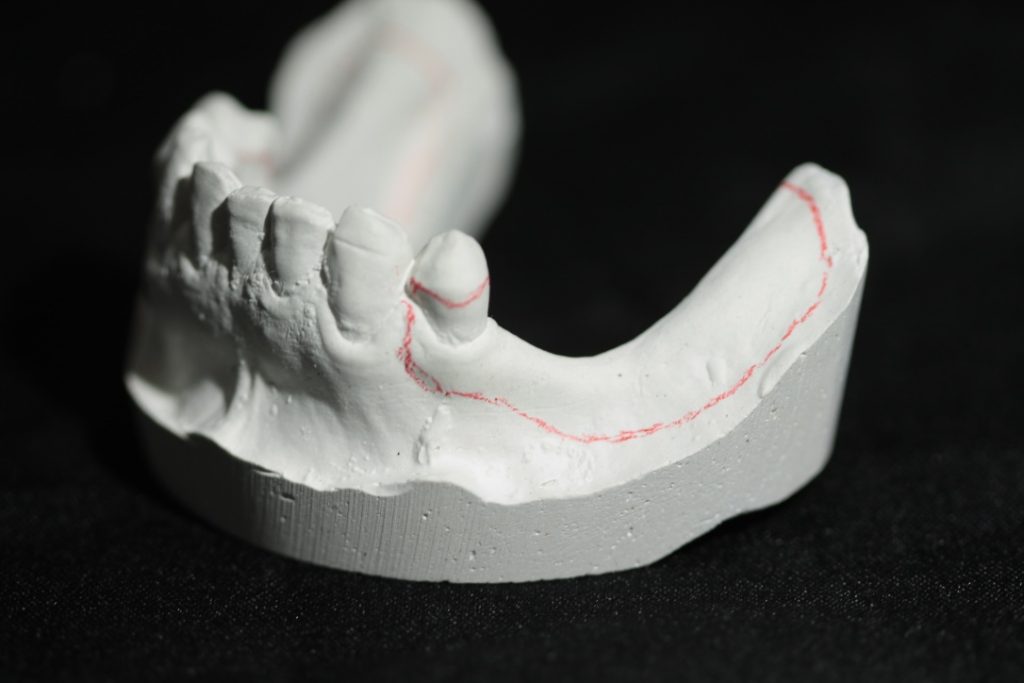

Design & Blockout Example

Watch an example of how to design and block out a difficult Kennedy Class I case.

Design for a case with long free end saddles.

The angulation of the teeth present a challenge with path of insertion.

Adding too much blockout could work against you in this case.